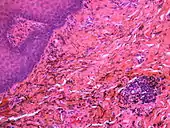

Granular deposits of silver sulfide along elastic fibers of the connective tissue of the oral mucosa. Low chronic inflammatory changes in the form of a lymphocytic aggregate (bottom right)

If necessary, the diagnosis can be confirmed histologically by excisional biopsy, which excludes nevi and melanomas.[3]:138 If a biopsy is taken, the histopathologic appearance is:[1]

• Pigmented fragments of metal within connective tissue

• Staining of reticulin fibers with silver salts

• A scattered arrangement of large, dark, solid fragments or a fine, black or dark brown granules

• Large particles may be surrounded by chronically inflamed fibrous tissue

• Smaller particles surrounded by more significant inflammation, which may be granulomatous or a mixture of lymphocytes and plasma cells